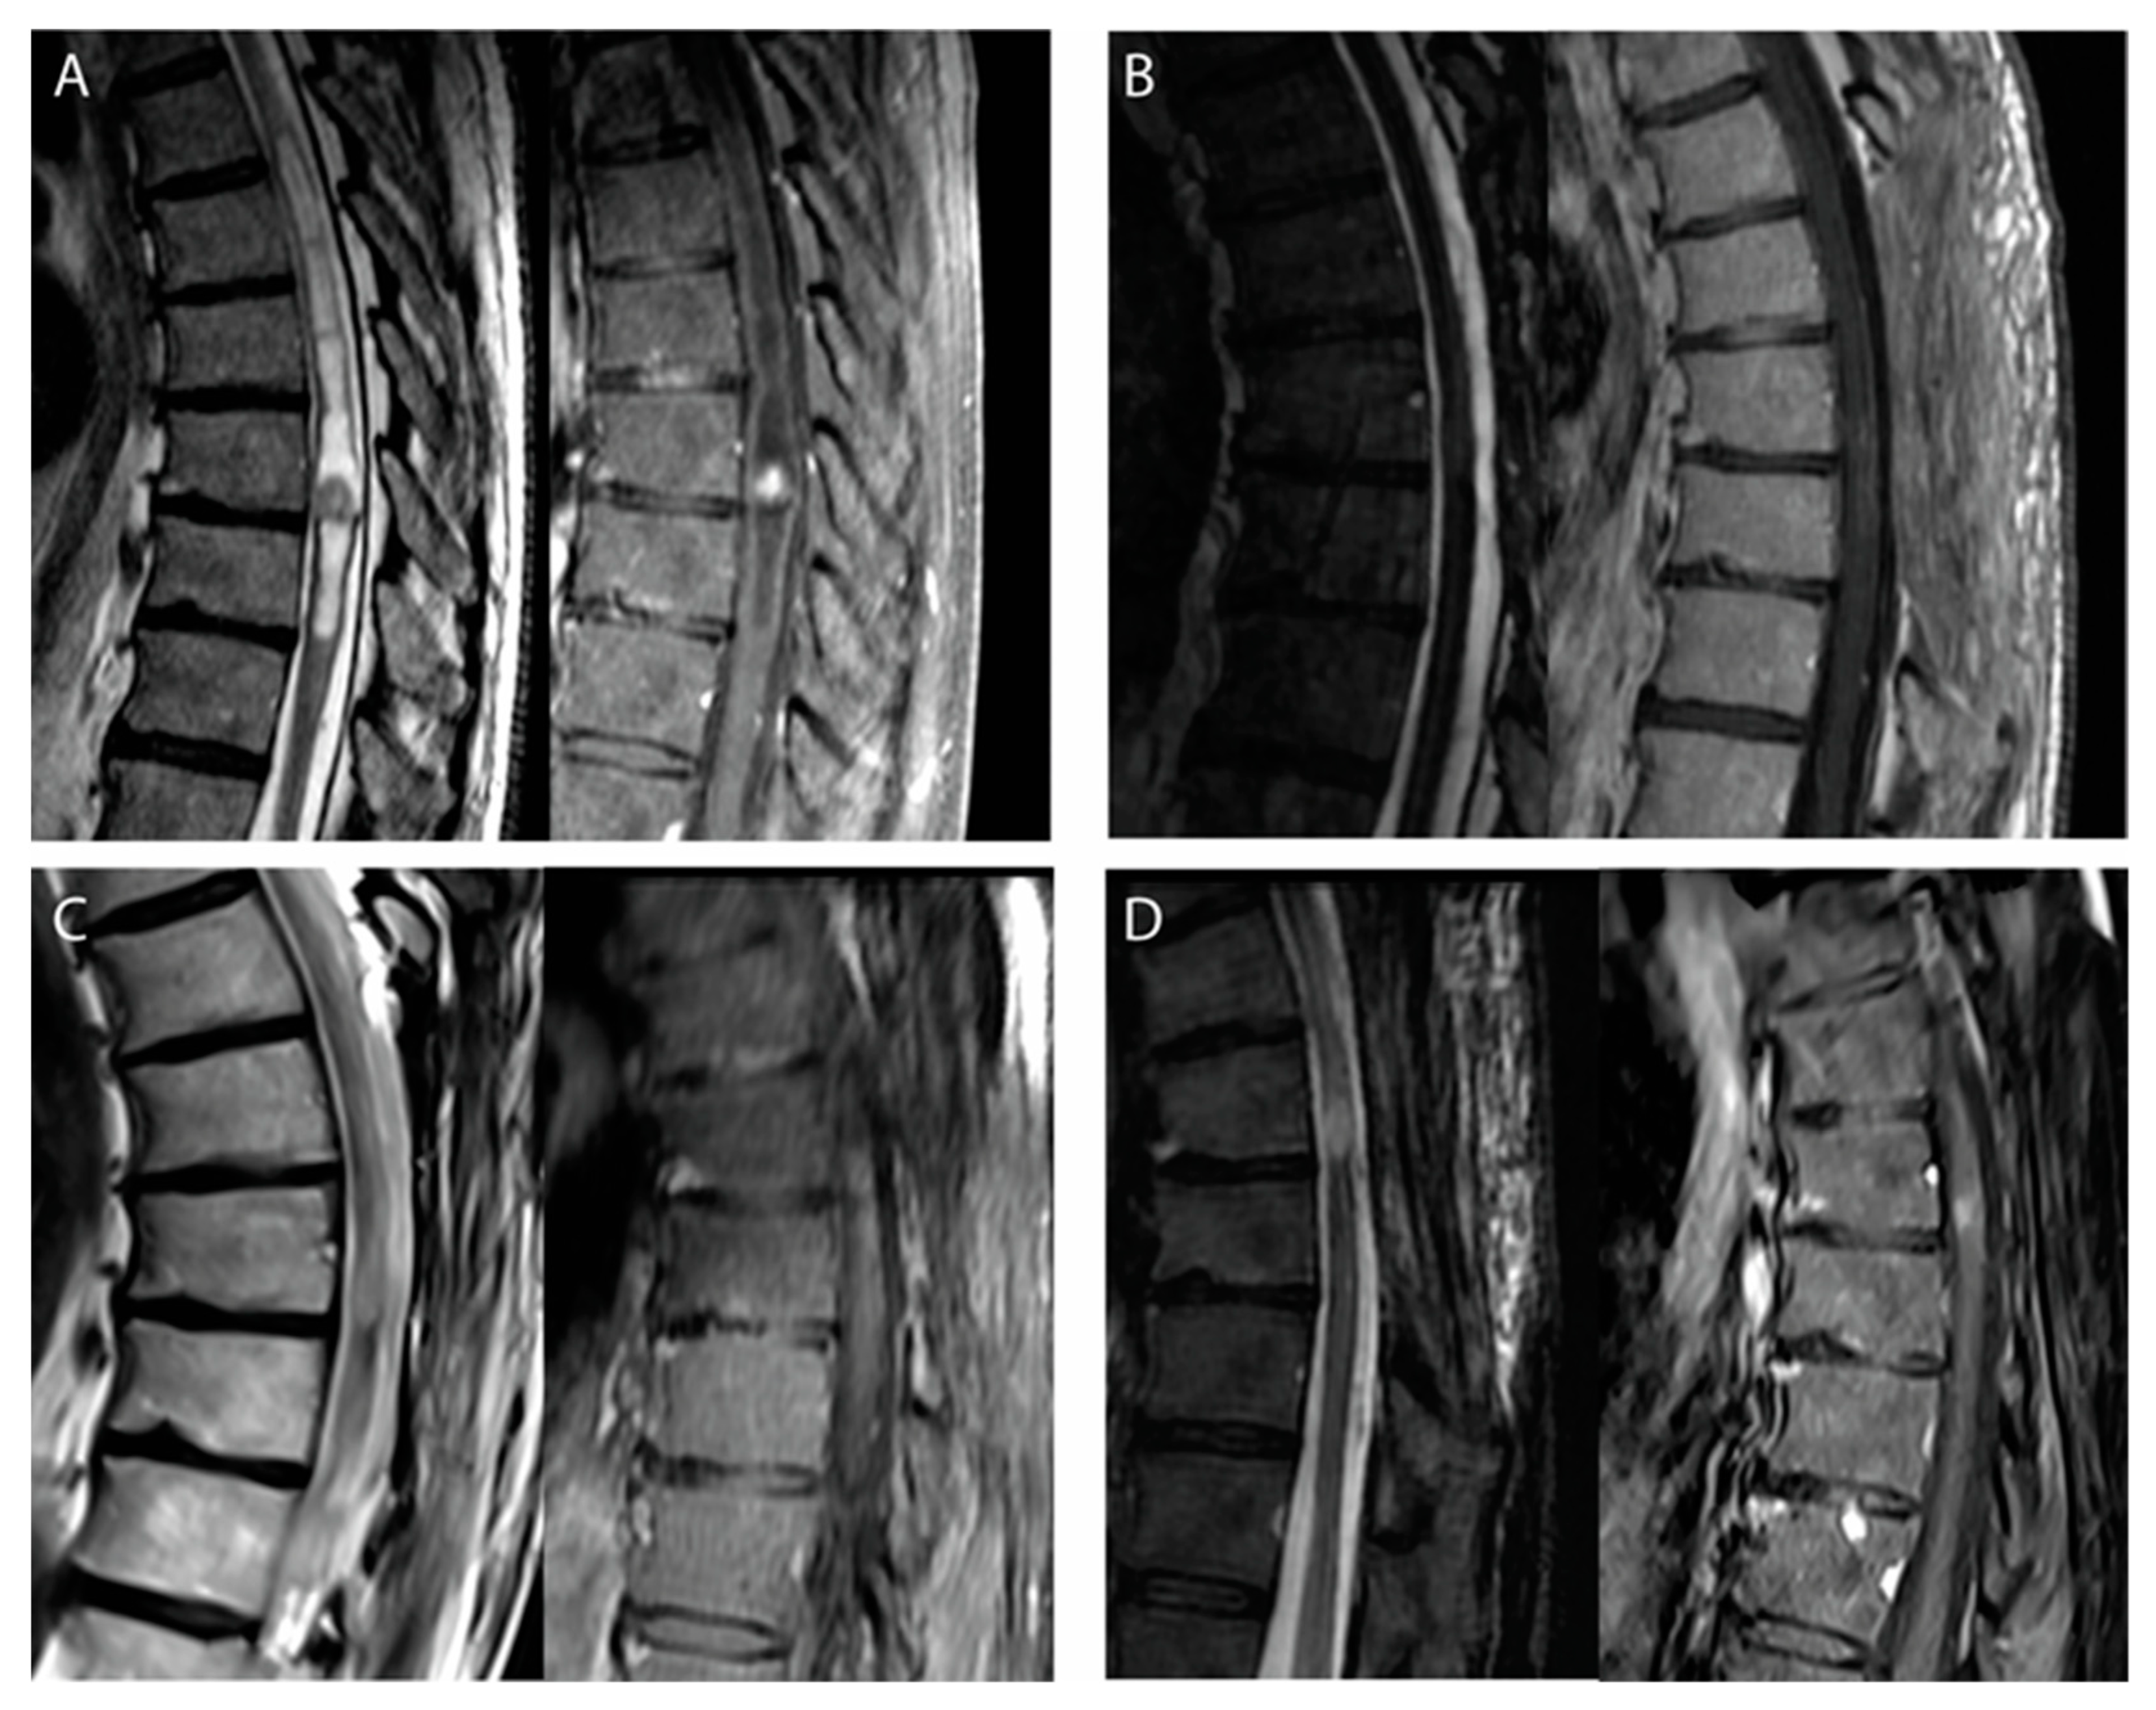

| T1-weighted sequence signal (%) | hypo | 54.8% |

| iso | 25.0% | |

| hyper | 16.1% | |

| T2-weighted sequence signal (%) | hypo | 17.1% |

| iso | 25.7% | |

| hyper | 57.1% | |

| Gadolinium enhancement | 100% | |

| Peritumoral cyst | 86.7% | |

| Peritumoral hemorrhage | 58.6% | |